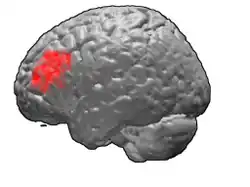

Brodmann area 46, or BA46, is part of the frontal cortex in the human brain. It is between BA10 and BA45.

BA46 is known as middle frontal area 46. In the human brain it occupies approximately the middle third of the middle frontal gyrus and the most rostral portion of the inferior frontal gyrus. Brodmann area 46 roughly corresponds with the dorsolateral prefrontal cortex (DLPFC), although the borders of area 46 are based on cytoarchitecture rather than function. The DLPFC also encompasses part of granular frontal area 9, directly adjacent on the dorsal surface of the cortex.

Lateral view.